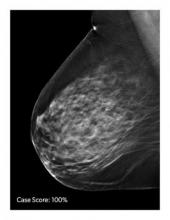

AI is also helping simplify complex tasks and help reduce the reading time on involved exams. One example of this is in 3-D breast tomosythesis with hundreds of images, which is rapidly replacing 2-D mammography, which only produces 4 images. Another example is automated image reconstruction algorithms to significantly reduce manual work. AI also is now being integrated directly into several vendors' imaging systems to speed workflow and improve image quality.

In addition to women with dense breasts, there are also other women for whom mammographic screening is not really enough, which is why research needs to continue in this field. Dr. Wendie Berg, a leading breast cancer specialist, talks with ITN about new research and advancements in breast imaging technology.